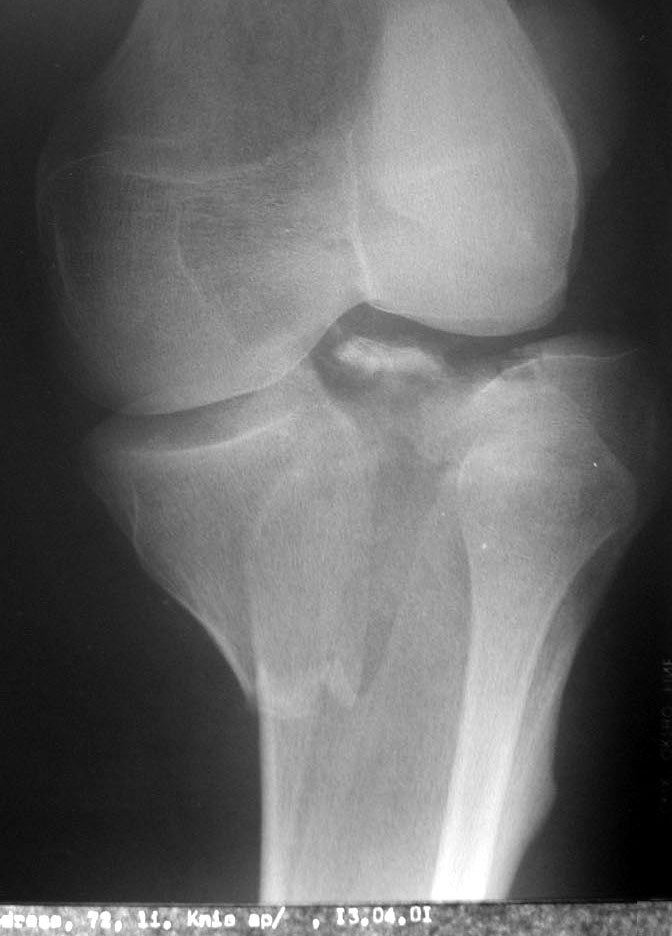

Auf dem Computertomogramm (3D-Rekonstruktion des Schienbeinkopfes bzw. Tibiaplateaus) sieht man schön die Bruchstelle des grossen Knochenfragmentes. Dummerweise geht der Bruch mitten durch die Kniegelenkfläche. Dazu kam noch ein sogenannter Impressionsbruch, hier nur für Profis erkennbar: Ein Teil der Gelenkfläche wurde durch die Gewalt des Sturzes in den Knochen hineingepresst.

Leider kommt das wegen der Beschaffenheit des Knochens nicht von selbst wieder hoch und musste angehoben sowie durch eine sogenannte Spongiosaplastik festgemacht werden (Knochenmaterial wurde aus dem Beckenkamm entnommen und im Knie unter das eingedrückte Stück wieder eingesetzt).

Als Vergleich: Wenn man den Finger in ein Stück Styropor drückt, bleibt auch ein Loch zurück. Dazu waren auch die Kreuzbandansätze angerissen.